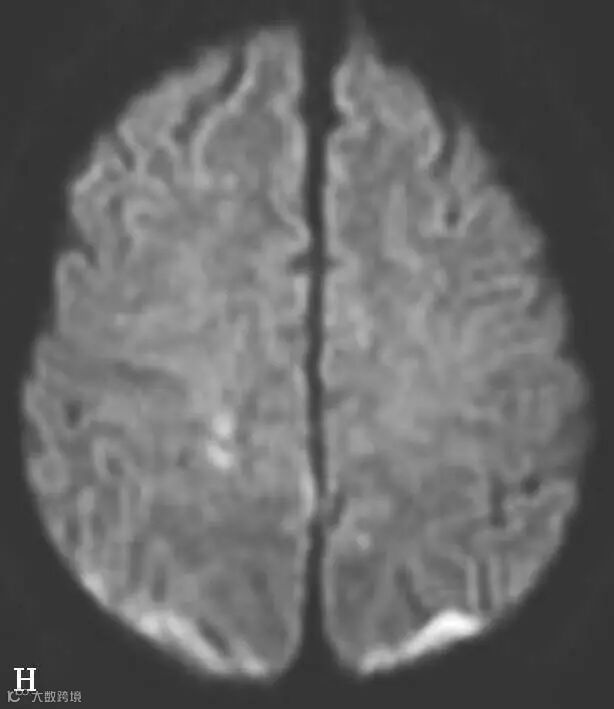

图6-11-2 弥漫性轴索损伤

男,36岁,外伤后2天。A~J(A、B.T2WI,C、D.T1WI,E、F.T2WI-FLAIR,G、H.DWI,I、J.ADC图):双侧额叶、半卵圆中心及胼胝体压部可见多发斑点状等T1稍长T2信号,边缘不清,FLAIR及DWI呈高信号,ADC图病灶信号减低 。